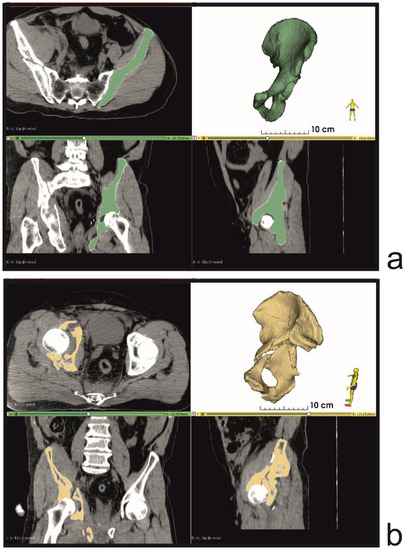

2. Materials and Methods

3. Results

- Segmentation and virtual planning;